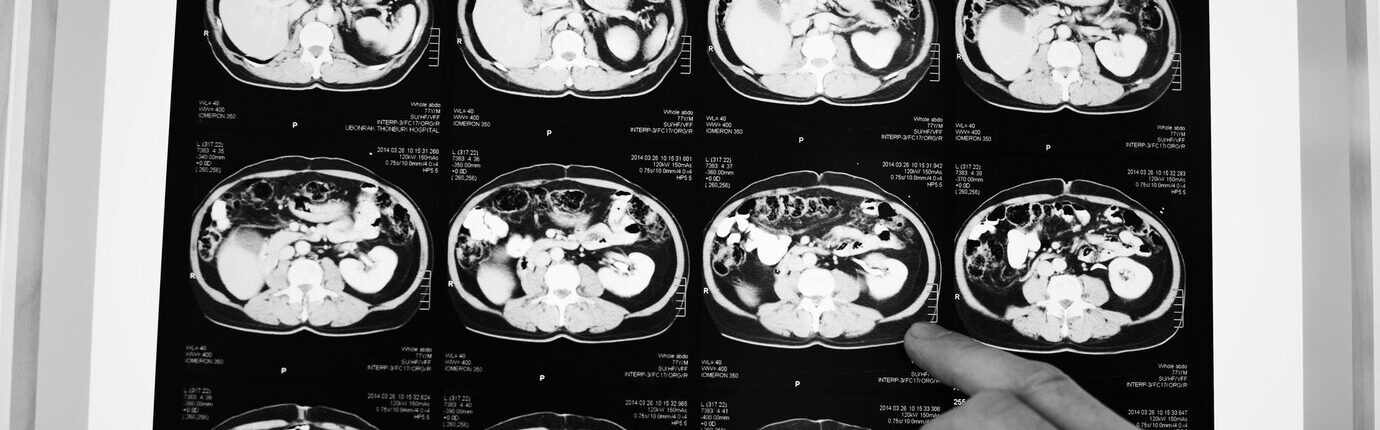

Brain tumours are identified using a CT or MRI scan. An expert who interprets scans (radiologist) will be able to see if you have an abnormality, which they may call a tumour.

MRI and CT scans

Below you will find information about MRI and CT scans, how they work and the differences between them:

CT scan – computerised tomography.

Instead of sending out a single x-ray through the body, several beams are sent simultaneously from different angles. The computer then processes the results showing them as a 2D picture. CT scans are less expensive and take less time than an MRI scan, but they have lower resolution so could potentially not show some skull base and low grade tumours, as well as an MRI scan. So, if you have one type of scan rather than another, it is usually because one will be more suited to you.

A CT scan usually lasts around 20 minutes and is quieter than an MRI scan. You lie on a table and the scanner moves around your head. If you need a contrast scan, then an iodine-based contrast agent will be injected. This shows the ‘leaky’ blood vessels in a tumour and enables the neuroradiologist to see the mass directly.